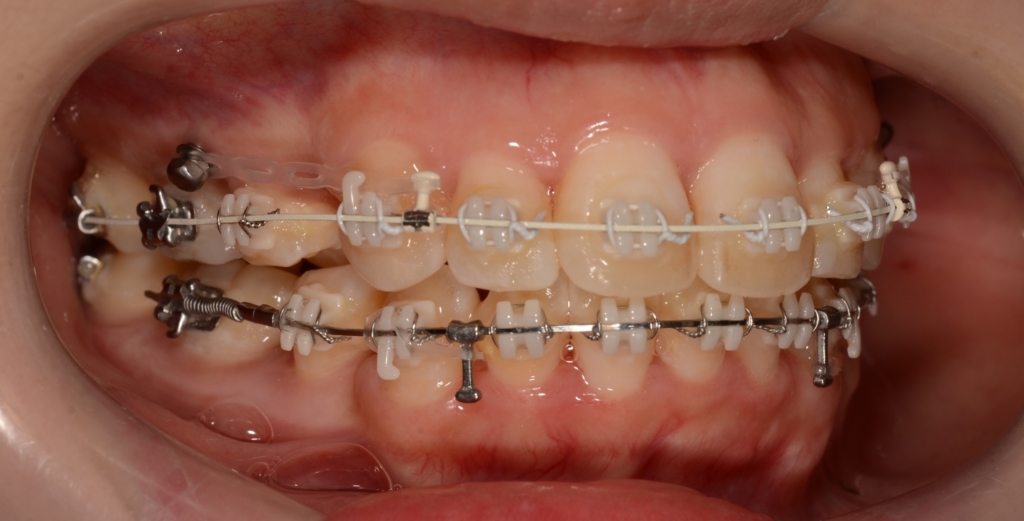

マルチブラケットシステム(ハーフホワイトtype)で矯正を開始。

*ハーフホワイトtype:上下とも歯の表側に白いブラケットを付けて、上には白いワイヤー&下には銀色のワイヤーを用いたストレートワイヤーによる歯列矯正

上下とも前歯はきれいに並びましたので、次のステップに移ります。

「口元がちょっとでも引っ込んで欲しい!」という」希望があったので、アンカースクリューを併用して治療を進めることにしました。